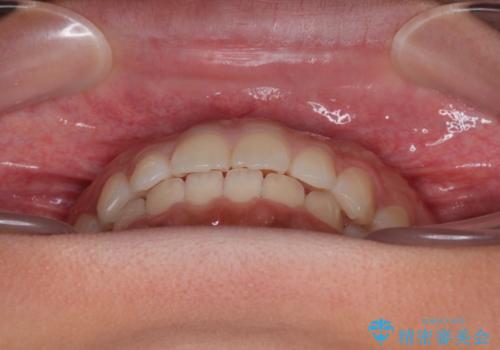

気になるすきっ歯を短期間で改善 インビザライン矯正

- 前歯の隙間を気にして来院された患者様です。

口元の突出感があり、小臼歯4本を抜歯して口元を引っ込める矯正治療も提案しましたが、本人は口元の突出感は気になっていないとのことで、インビザラインにて隙間やデコボコを改善することとしました。

軽度の歯列不正であったため、廉価版のインビザライン・モデレートパッケージにて治療を終えることができました。